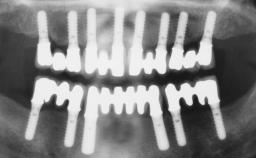

Rehabilitating an Edentulous Maxilla with a Fixed Dental Prosthesis Following Provisional Immediate Loading

This case features the flapless computer-guided placement of 7 bone-level implants, distributed to provide maximal support for the prosthetic framework. A rigid one-piece metallic framework was utilized as an interim restoration to reduce the risk of fracture associated with this prosthetic design. As part of the clinical examination, the SAC Assessment Tool was used, resulting in a surgical and restorative risk classification as “complex”.

# of Implants 7

Guided Surgery Yes

Modality 6+ implants with immediate loading